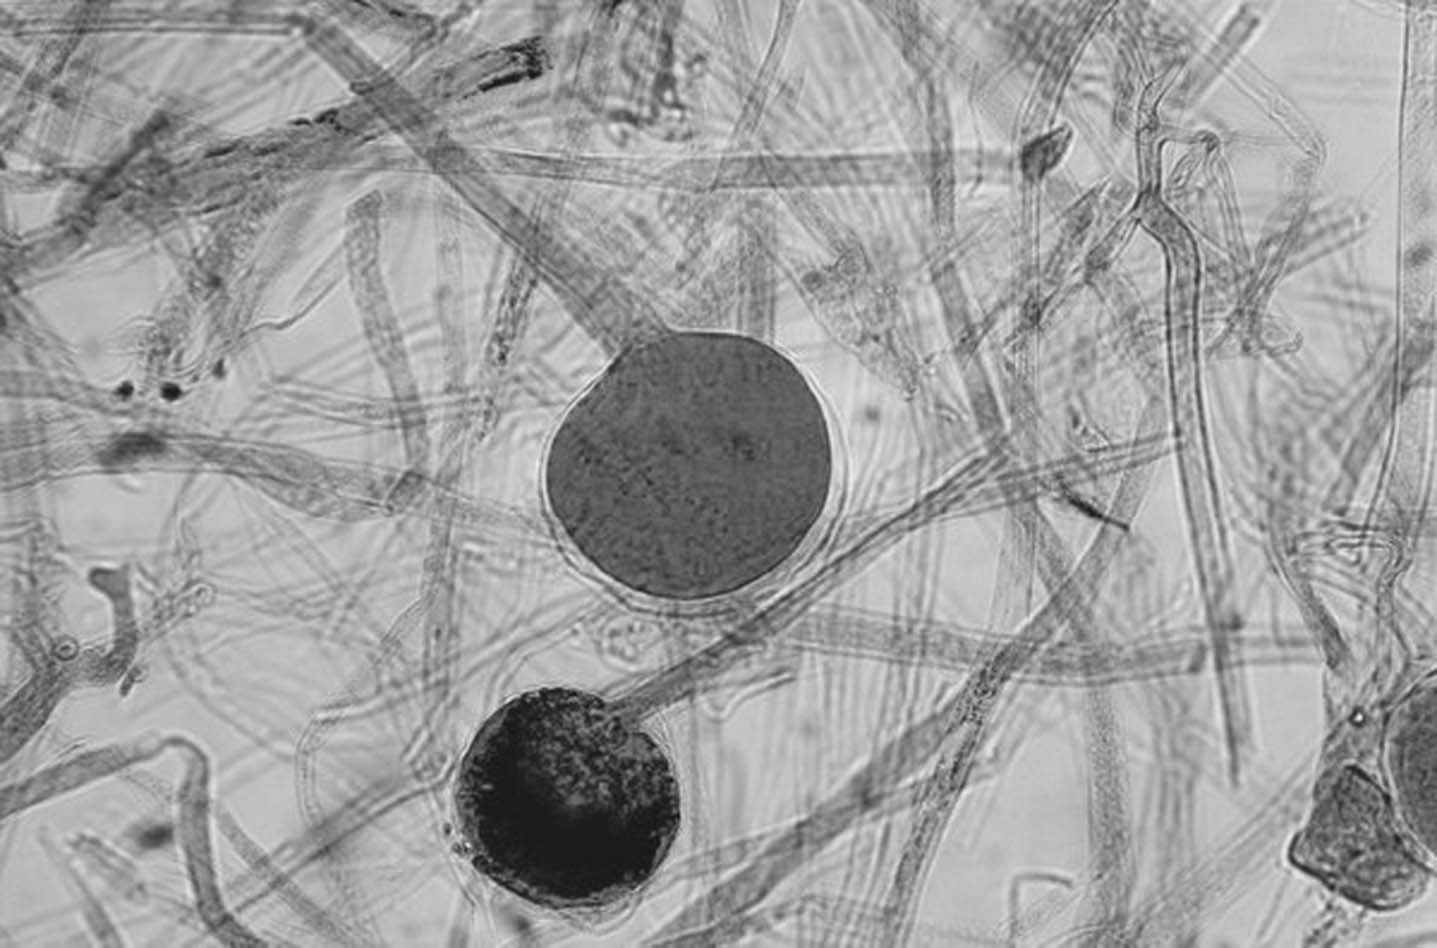

吞噬细胞作为宿主的防御机制之一,其数量和功能在急性侵袭型肺曲霉病的发病中具有重要意义。淋巴细胞介导的细胞免疫也是重要的。实验研究证明,中性粒细胞可阻止曲霉菌丝的形成,而单核细胞则主要影响分生孢子。这与临床上本病好发于粒细胞缺乏和细胞免疫损害患者是吻合的。体液免疫在本病发病机制中的作用不清楚。在丙种球蛋白缺乏或功能紊乱患者本病发生率并无增加,提示体液免疫不起主要作用。病理表现主要为急性坏死性出血性肺炎。炎性浸润、化脓,进而形成肉芽肿。菌丝在肺内增殖和侵入血管,导致坏死性血管炎,造成血栓或菌栓,引起咯血和血行播散,在脑、肝、肾、心脏等脏器产生曲霉感染。肺外曲霉脓肿、菌栓的血行播散有时也可引起肺内感染病灶。